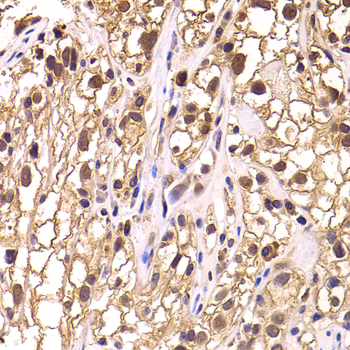

• A6994: image 2

Immunohistochemistry of paraffin-embedded human kidney cancer using TCEB3 antibody at dilution of 1:100 (x400 lens).